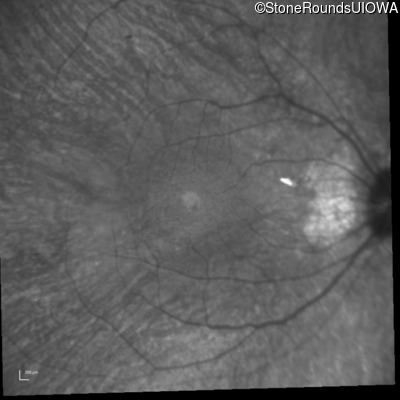

Infrared Fundus Photograph - Right - 20/30 +2

Exemplar

Infrared Fundus Photograph - Left - 20/20 -2